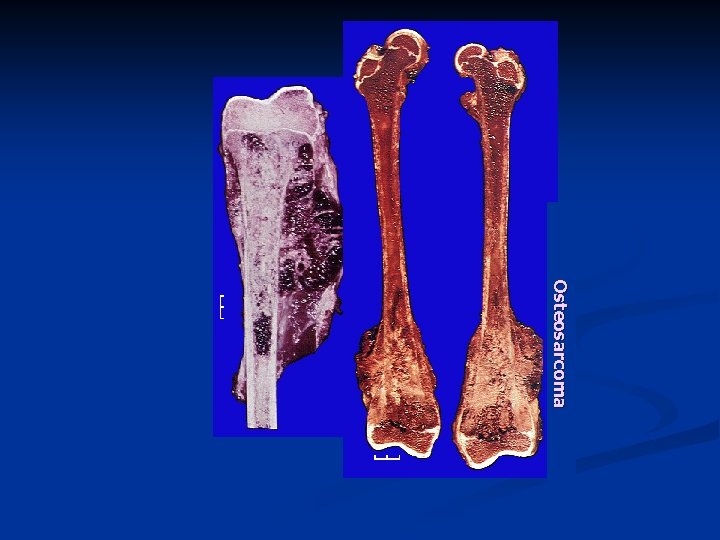

Osteogenic Sarcoma Osteosarcoma: a malignant tumor of bone n Most common primary bone tumor after myeloma n

In young people under 20 years of age n Male / Female : 2/1 n n Peak beyond 40 years of age: n Secondary to preexisting disease n Paget's disease (Paget's sarcoma) n Previous radiation (irradiation sarcoma) n Other conditions

n n Osteosarcoma may occur in any bone The most frequent location is near the knee (~50 -60% of cases) n n n most commonly in the distal end of the femur the upper end of the tibia, upper end of the humerus, pelvis, upper end of the femur. Bone-forming cells produce alkaline phosphatase n The serum alkaline phosphatase is markedly elevated in many patients with osteosarcoma.

Osteosarcoma